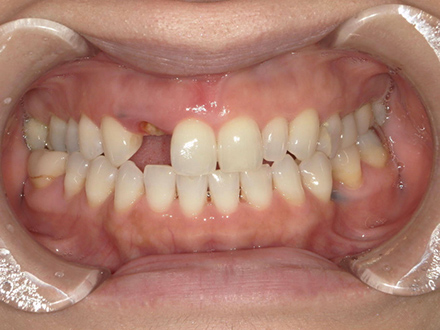

| 治療部位 | 上顎前歯部 |

|---|---|

| インプラント本数 | 4本 |

| 単価 | 40万円/本 |

| 合計費用 | 160万円 |